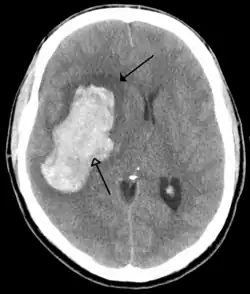

Tumours

Brain tumours can be either benign or cancerous. Most malignant tumours arise from another part of the body, most commonly from the lung, breast and skin.[178] Cancers of brain tissue can also occur, and originate from any tissue in and around the brain. Meningioma, cancer of the meninges around the brain, is more common than cancers of brain tissue.[178] Cancers within the brain may cause symptoms related to their size or position, with symptoms including headache and nausea, or the gradual development of focal symptoms such as gradual difficulty seeing, swallowing, talking, or as a change of mood.[178] Cancers are in general investigated through the use of CT scans and MRI scans. A variety of other tests including blood tests and lumbar puncture may be used to investigate for the cause of the cancer and evaluate the type and stage of the cancer.[178] The corticosteroid dexamethasone is often given to decrease the swelling of brain tissue around a tumour. Surgery may be considered, however given the complex nature of many tumours or based on tumour stage or type, radiotherapy or chemotherapy may be considered more suitable.[178]

Stroke

A stroke is a decrease in blood supply to an area of the brain causing cell death and brain injury. This can lead to a wide range of symptoms, including the "FAST" symptoms of facial droop, arm weakness, and speech difficulties (including with speaking and finding words or forming sentences).[191] Symptoms relate to the function of the affected area of the brain and can point to the likely site and cause of the stroke. Difficulties with movement, speech, or sight usually relate to the cerebrum, whereas imbalance, double vision, vertigo and symptoms affecting more than one side of the body usually relate to the brainstem or cerebellum.[192]

Most strokes result from loss of blood supply, typically because of an embolus, rupture of a fatty plaque causing thrombus, or narrowing of small arteries. Strokes can also result from bleeding within the brain.[193] Transient ischaemic attacks (TIAs) are strokes in which symptoms resolve within 24 hours.[193] Investigation into the stroke will involve a medical examination (including a neurological examination) and the taking of a medical history, focusing on the duration of the symptoms and risk factors (including high blood pressure, atrial fibrillation, and smoking).[194] Further investigation is needed in younger patients.[195] An ECG and biotelemetry may be conducted to identify atrial fibrillation; an ultrasound can investigate narrowing of the carotid arteries; an echocardiogram can be used to look for clots within the heart, diseases of the heart valves or the presence of a patent foramen ovale.[195] Blood tests are routinely done as part of the workup including diabetes tests and a lipid profile.[195]

Some treatments for stroke are time-critical. These include clot dissolution or surgical removal of a clot for ischaemic strokes, and decompression for haemorrhagic strokes.[196][197] As stroke is time critical,[198] hospitals and even pre-hospital care of stroke involves expedited investigations – usually a CT scan to investigate for a haemorrhagic stroke and a CT or MR angiogram to evaluate arteries that supply the brain.[195] MRI scans, not as widely available, may be able to demonstrate the affected area of the brain more accurately, particularly with ischaemic stroke.[195]